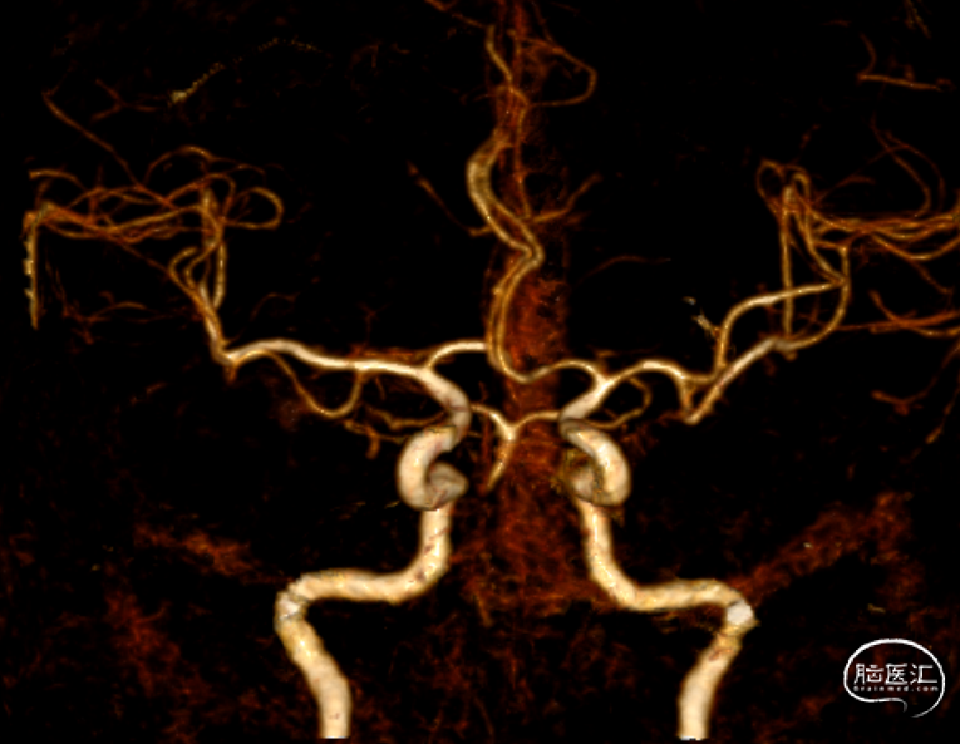

入院头颅CTA(2022-2-2)

头颈部CTA:右侧椎动脉纤细,双侧椎动脉末端、基底动脉起始段消失,考虑闭塞,请结合临床。

1、患者入院时症状较轻,头颈部CTA示:双侧椎动脉V4段及基底动脉中下段未显影,基底动脉上段、双侧大脑后动脉及小脑上动脉显影,考虑基底动脉存在原位狭窄或慢性闭塞,入院后患者病情进展,症状加重,积极行介入治疗。